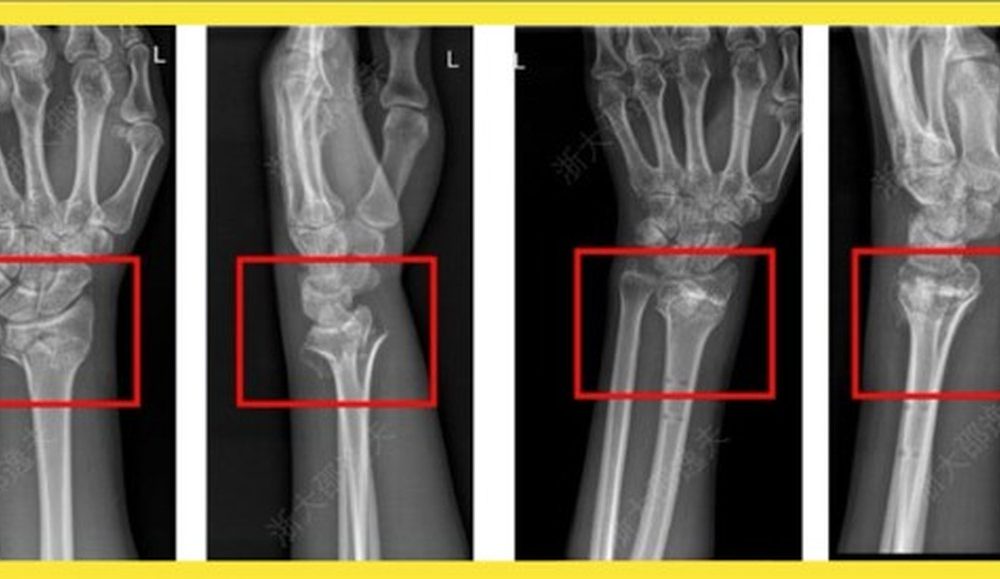

Em caso experimental, um paciente com fratura no punho recebeu uma injeção através de uma incisão de apenas 3 cm e foi curado em apenas três minutos, informou o “Cho Sun Daily”. Uma cirurgia para reparar o punho exigiria uma placa metálica e parafusos, cuja remoção exigiria uma segunda cirurgia no ano seguinte. Após um check-up de acompanhamento de três meses, a fratura do paciente havia cicatrizado completamente sem complicações, afirmou a reportagem.